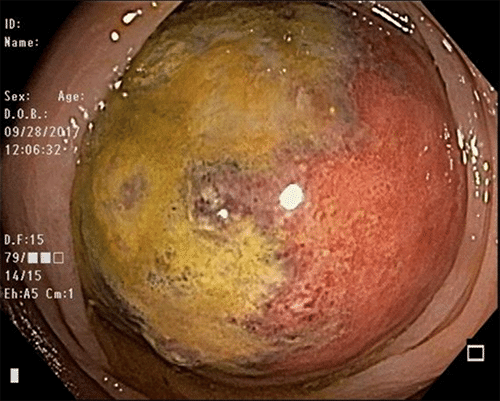

Our differential diagnosis at this time included malignant neoplasm, gastrointestinal stromal tumor (GIST), or intestinal lipoma. The patient was admitted and underwent mechanical bowel preparation. An approximately 6 cm circular nonobstructing submucosal mass was identified at colonoscopy in the sigmoid colon (Figure 2). Additional findings included three polyps in the hepatic flexure, descending colon, and rectum, all of which were consistent with tubular adenomas upon final pathologic examination. With the patient in stable condition, laparoscopic segmental sigmoid resection with hand assist and primary anastomosis was performed the following day without complication. A large mid-sigmoid mass lesion was identified with surrounding inflammatory changes consistent with intussusception (Figure 3). The postoperative course of the patient was uncomplicated. He required minimal intravenous analgesia and was started on a clear liquid diet following the procedure. He was discharged on postoperative day one following adequate pain control with minimal oral medications, once tolerating a general diet and demonstrating regular bowel function. The final pathologic review confirmed a 5 cm submucosal lipoma with focal fat necrosis and mucosal overlying ulceration (Figure 4).

Figure 2. Endoscopic View of Sigmoid Colon At 35 Cm Demonstrating Large, Firm, Circular Mass with Normal Overlying Mucosa. Published With Permission